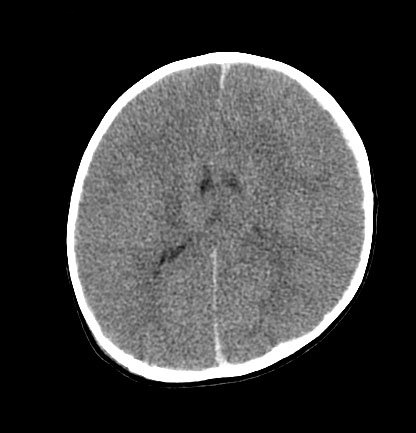

CT findings in fatal abusive head trauma often reveal significant brain oedema with loss of grey-white differentiation and effacement of the ventricles. Subdural blood is often difficult to appreciate in such cases

From the personal collection of Alice Newton, MD; used with permission